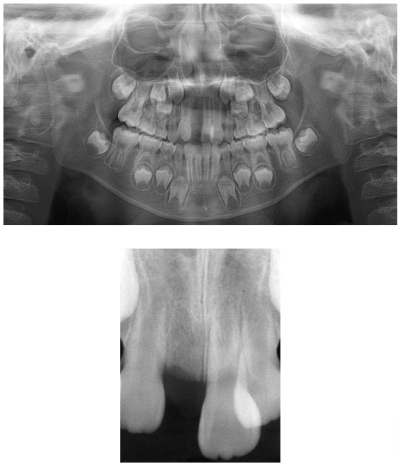

9歳の男児。審美不良を主訴として来院した。2か月前に外傷によって上顎右側中切歯が脱落し、傷は治ったが、そのままにした場合にどうなるか心配しているという。初診時の口腔内写真とエックス線画像を別に示す。